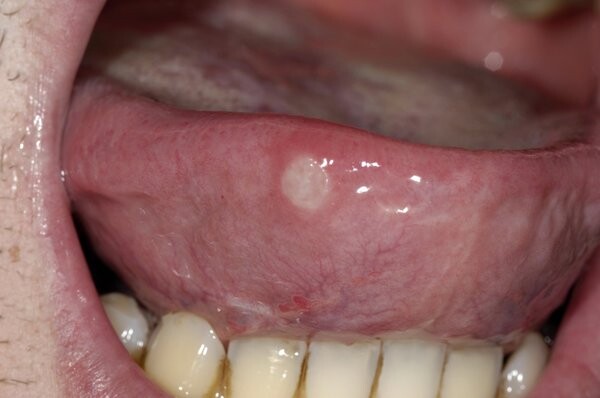

larger, with a white or gray center and red edges

Canker sores, or mouth ulcers, are small harmless sores that can appear on the tongue. The symptoms of canker sores include:

small sores that begin as a red bump and then develop a white or gray center with flat red edges